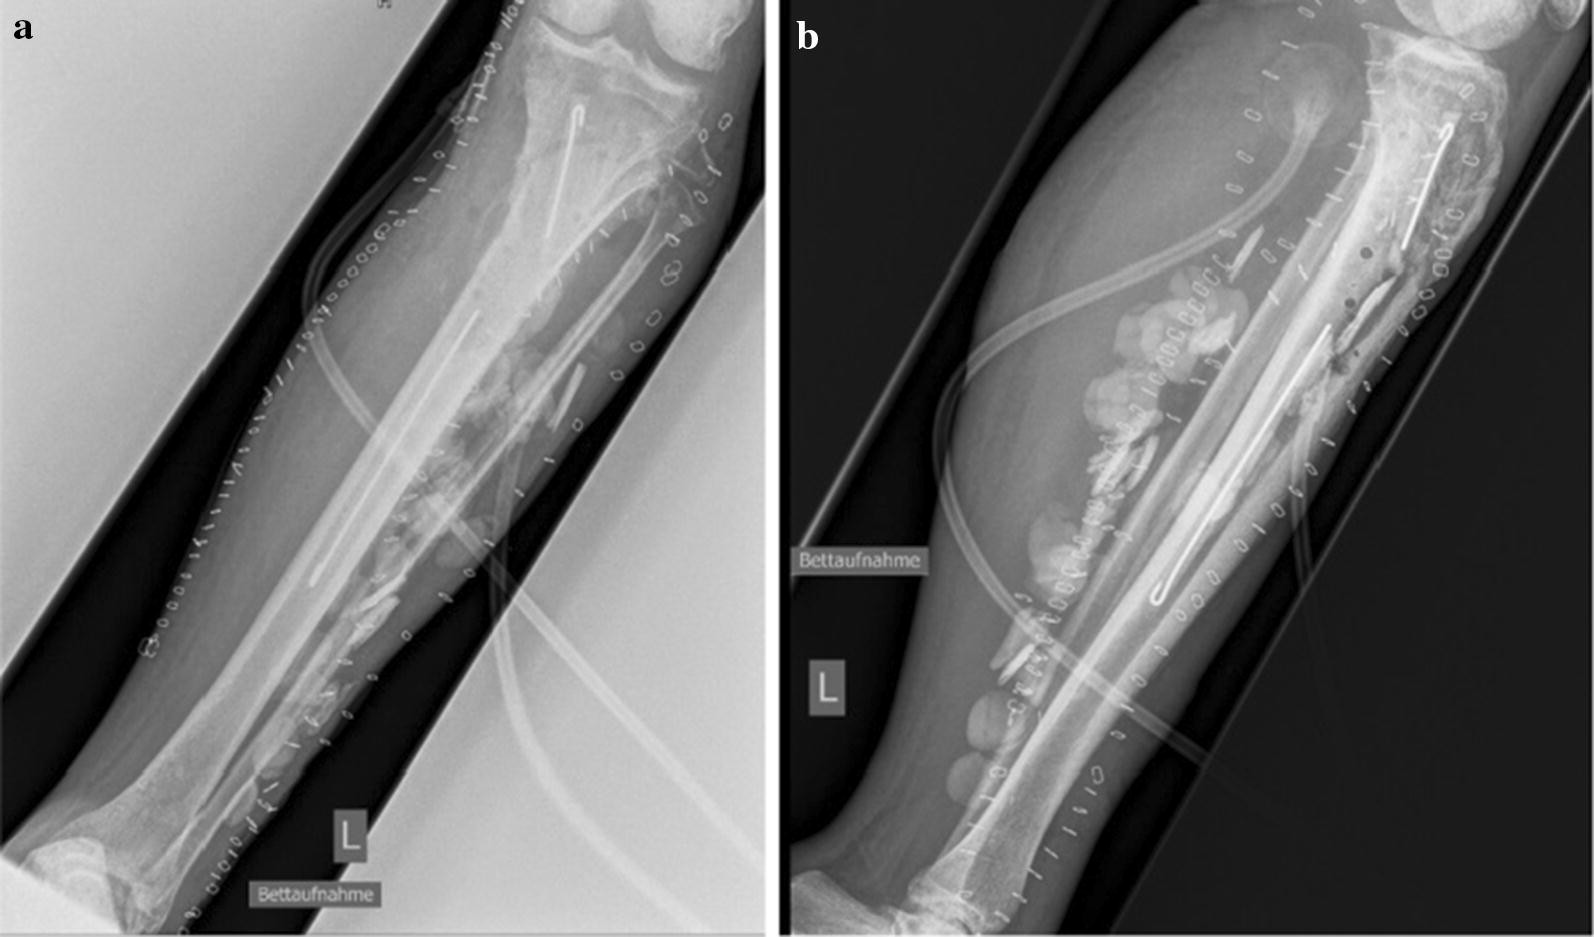

Fig. 5From: Eradication of Acinetobacter baumannii/Enterobacter cloacae complex in an open proximal tibial fracture and closed drop foot correction with a multidisciplinary approach using the Taylor Spatial Frame®: a case reportPlain X-rays showing reamed intramedullary zone, implanted spacer (sticks and chains) as well as negative pressure wound therapy in situ. a X-ray a.p. view and b X-ray lateral viewBack to article page